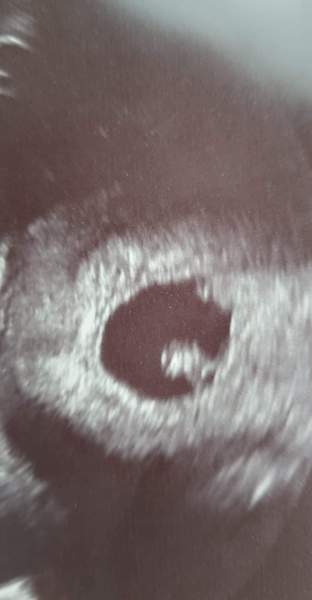

Yes, all great news, strong healthy heartbeat, perfect little bean, we are so happy and relieved! :) She found it right away and said look there it is, impossible to miss!

Oh that's wonderful news @Lily999 ! 🥰 Congrats on the scan and lovely picture

@Lily999 congratulations! Beautiful scan!

Beautiful scan pic @Lily999 😍 Did they give you a preliminary EDD?x

Thank you @minster2012, @Chooklass, @GoldenCloud, @QuantumGirl, when the midwife came in and said: look at that strong heartbeat, that's exactly what we want to see now. :) My heart wanted to explode, it was unreal.

The nurse said when we started: it might take me a while to find my way so don't be alarmed, but then about 2second later she said wow, there we are! :)

DH was staring at this photo for minutes afterwards trying to figure out if it's a girl or a boy that made me chuckle :D :D :D

Congratulations @Lily999 that is a great picture! 🤩❤️

Welcome and congrats @Russkispy and lovely scan pic @Lily999 ❤️